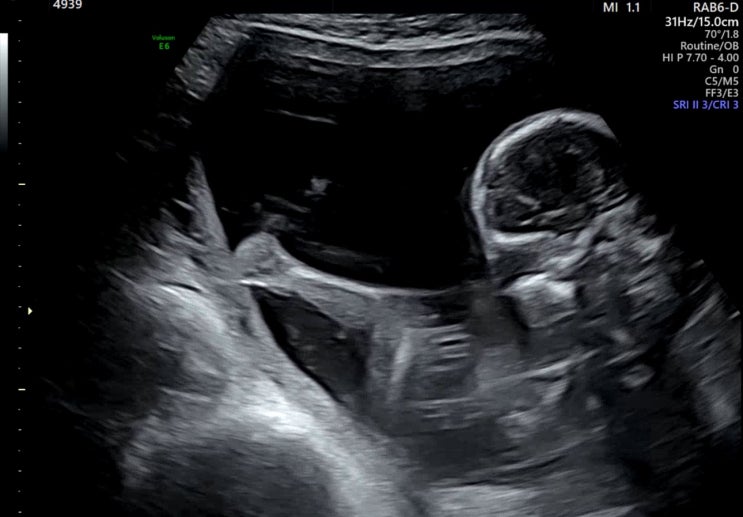

임신일기#4 :: 20주~26주 태아 수신증 신우확장증,입체초음파 시기

임신 중기에 들어서면서, 이제 안정기라고 마음 놓고 지내고 있었거든요 20주때 산부인과가서 정밀초음파를...